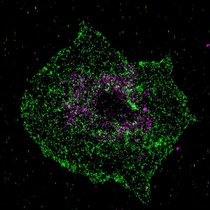

Das bislang weitgehend unbekannte Molekül namens bridging integrator 2 (BIN2) spielt bei der Aktivierung der Blutplättchen eine zentrale Rolle, wie…

Das bislang weitgehend unbekannte Molekül namens bridging integrator 2 (BIN2) spielt bei der Aktivierung der Blutplättchen eine zentrale Rolle, wie…